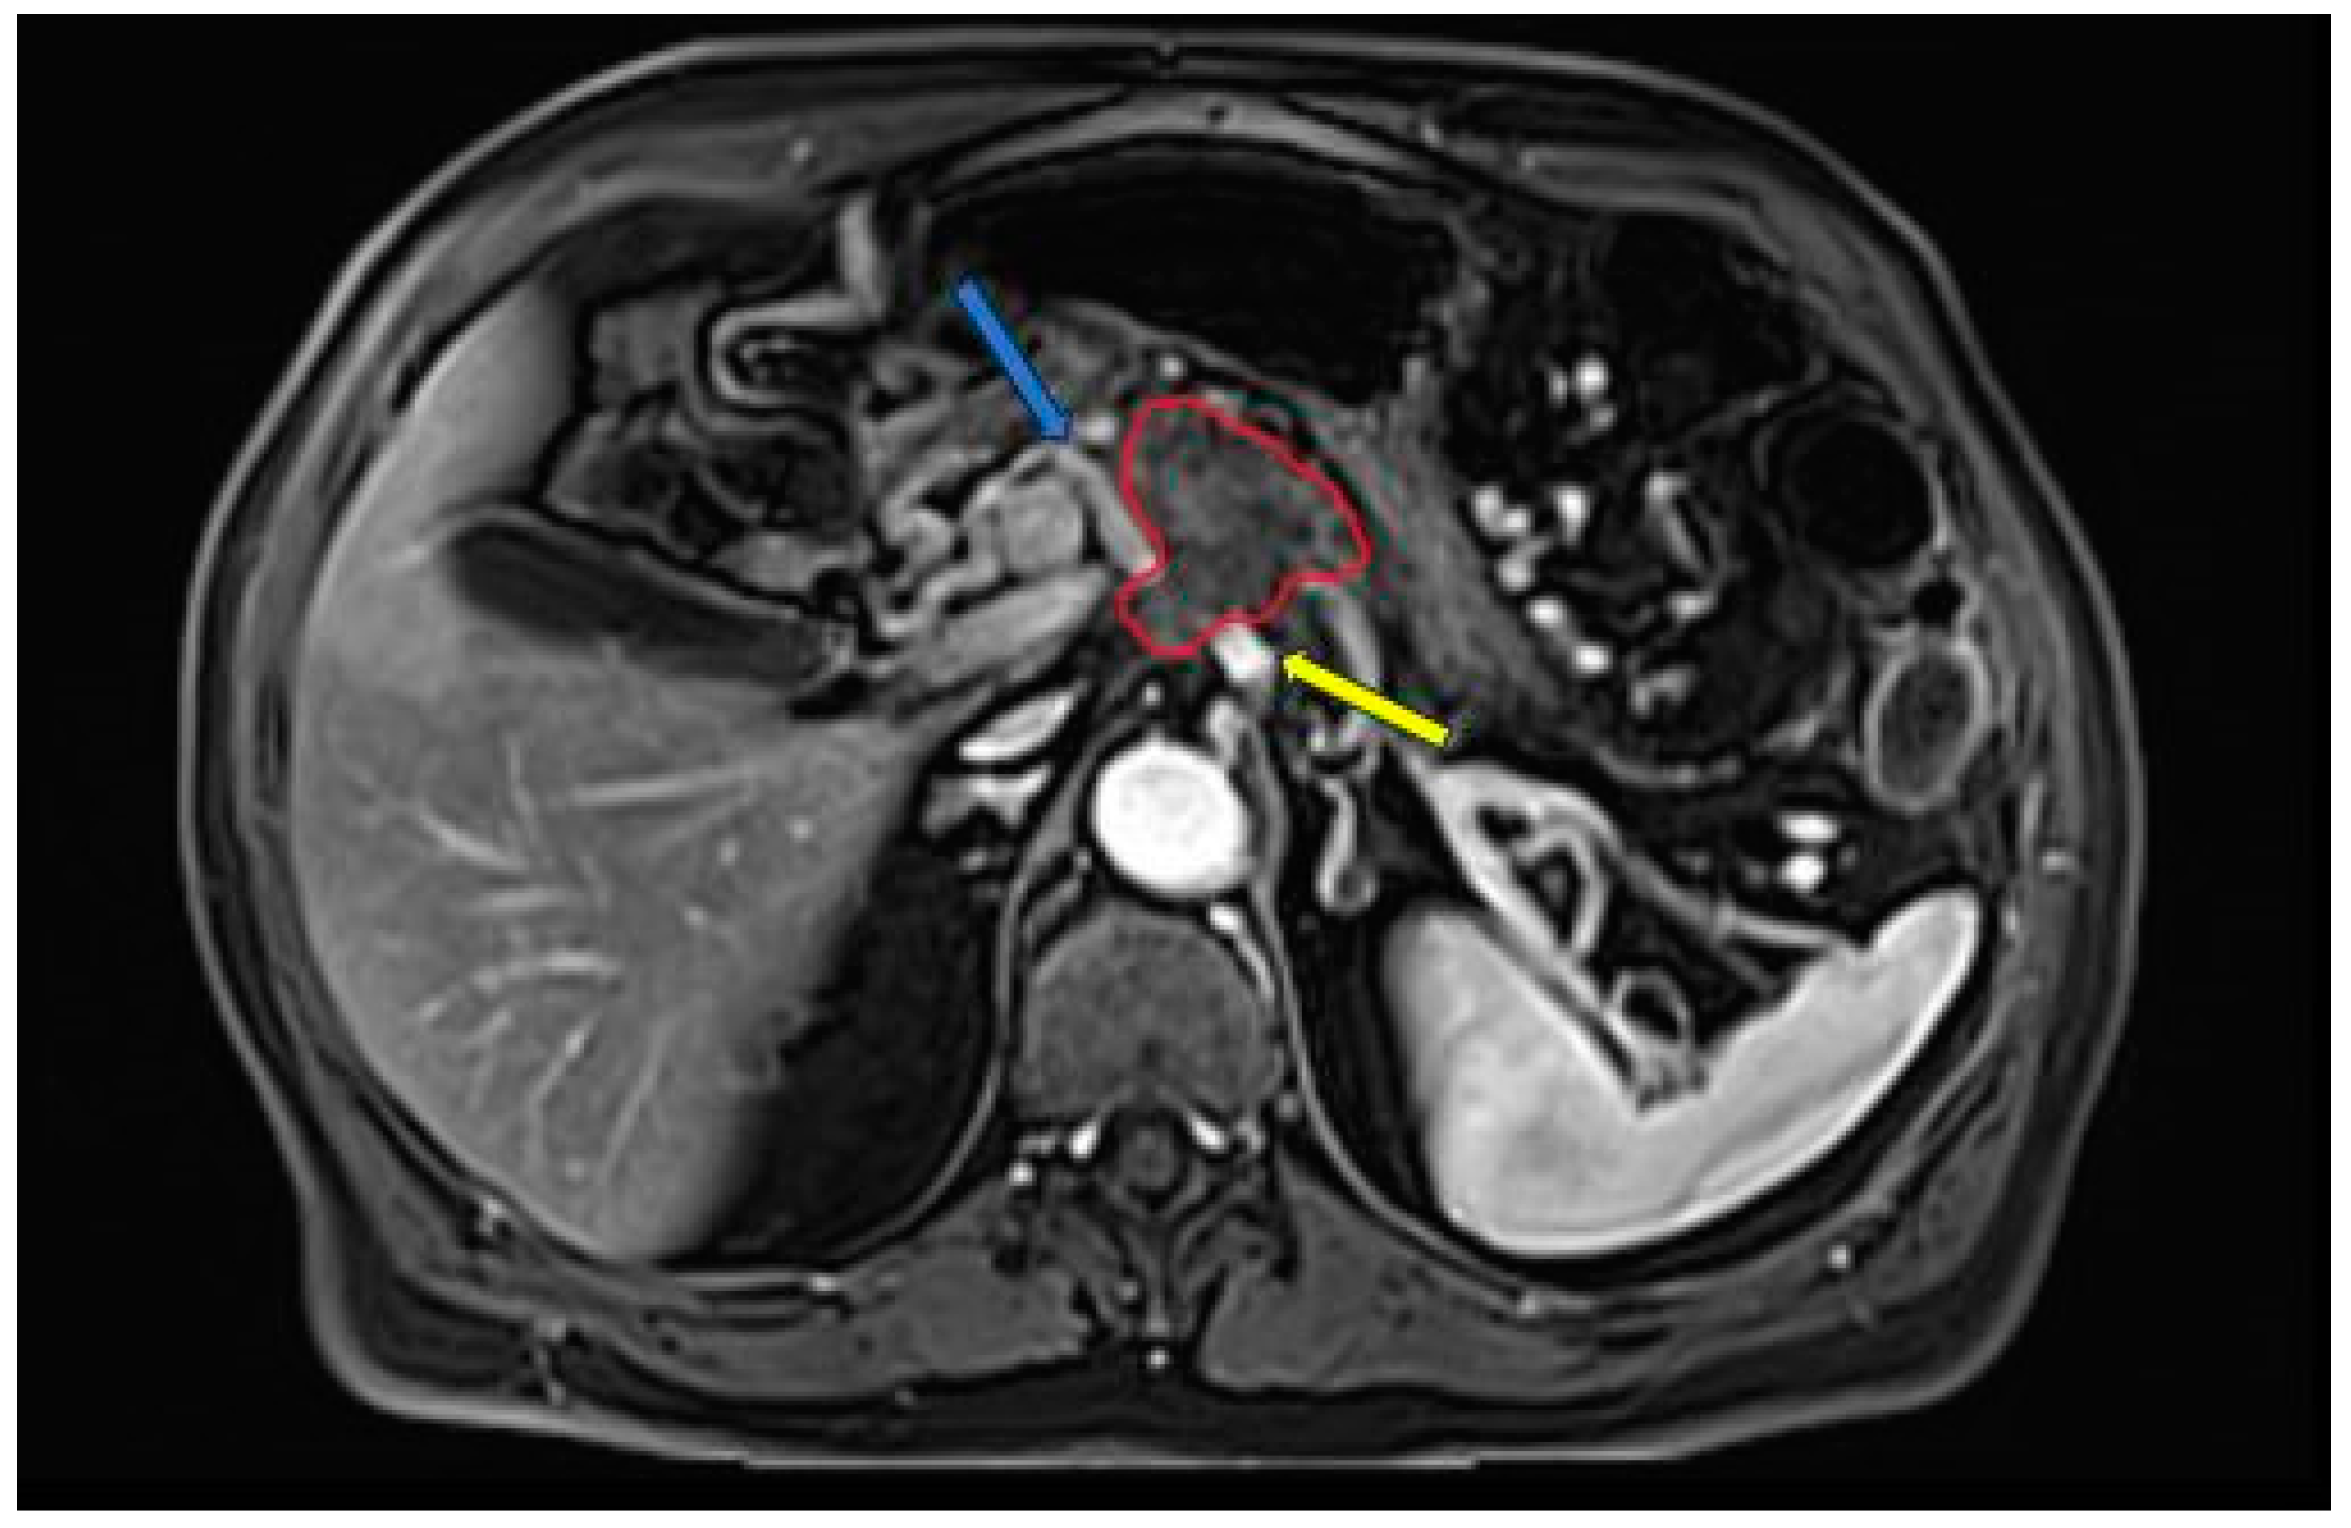

2. Imaging Modalities